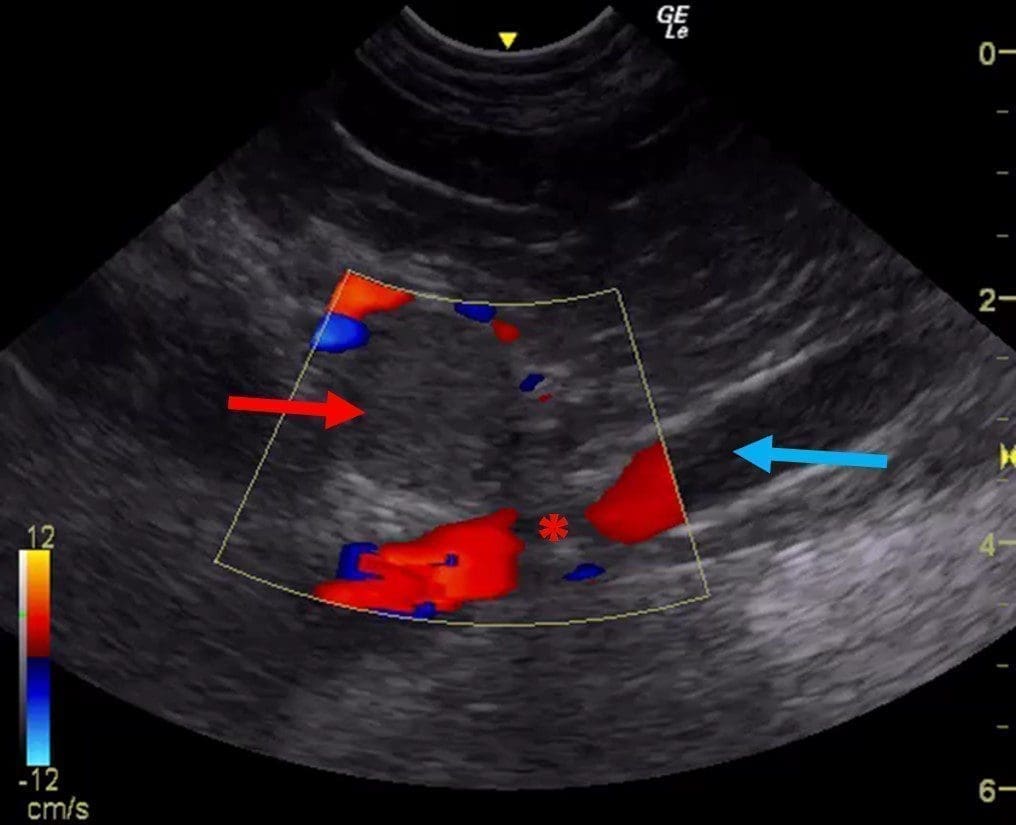

Ultrasonography of the Abdominal Vessels >>